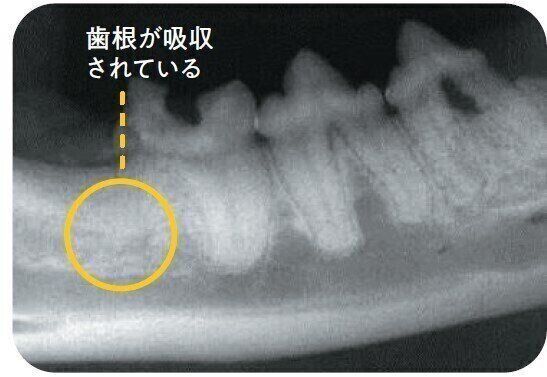

歯冠も歯根も溶け、骨組織に吸収されるタイプ。中央の歯の歯根の輪郭が確認できますが、右の歯の歯根は溶けて輪郭がなくなっており、骨組織に置き換わっています。

タイプ3

タイプ1とタイプ2が併発しているタイプ。1つの歯に2つの歯根がある場合、片方の歯根のみ吸収されている状態。写真の左端の歯は、左側の歯根のみ吸収され、骨と同化しています。